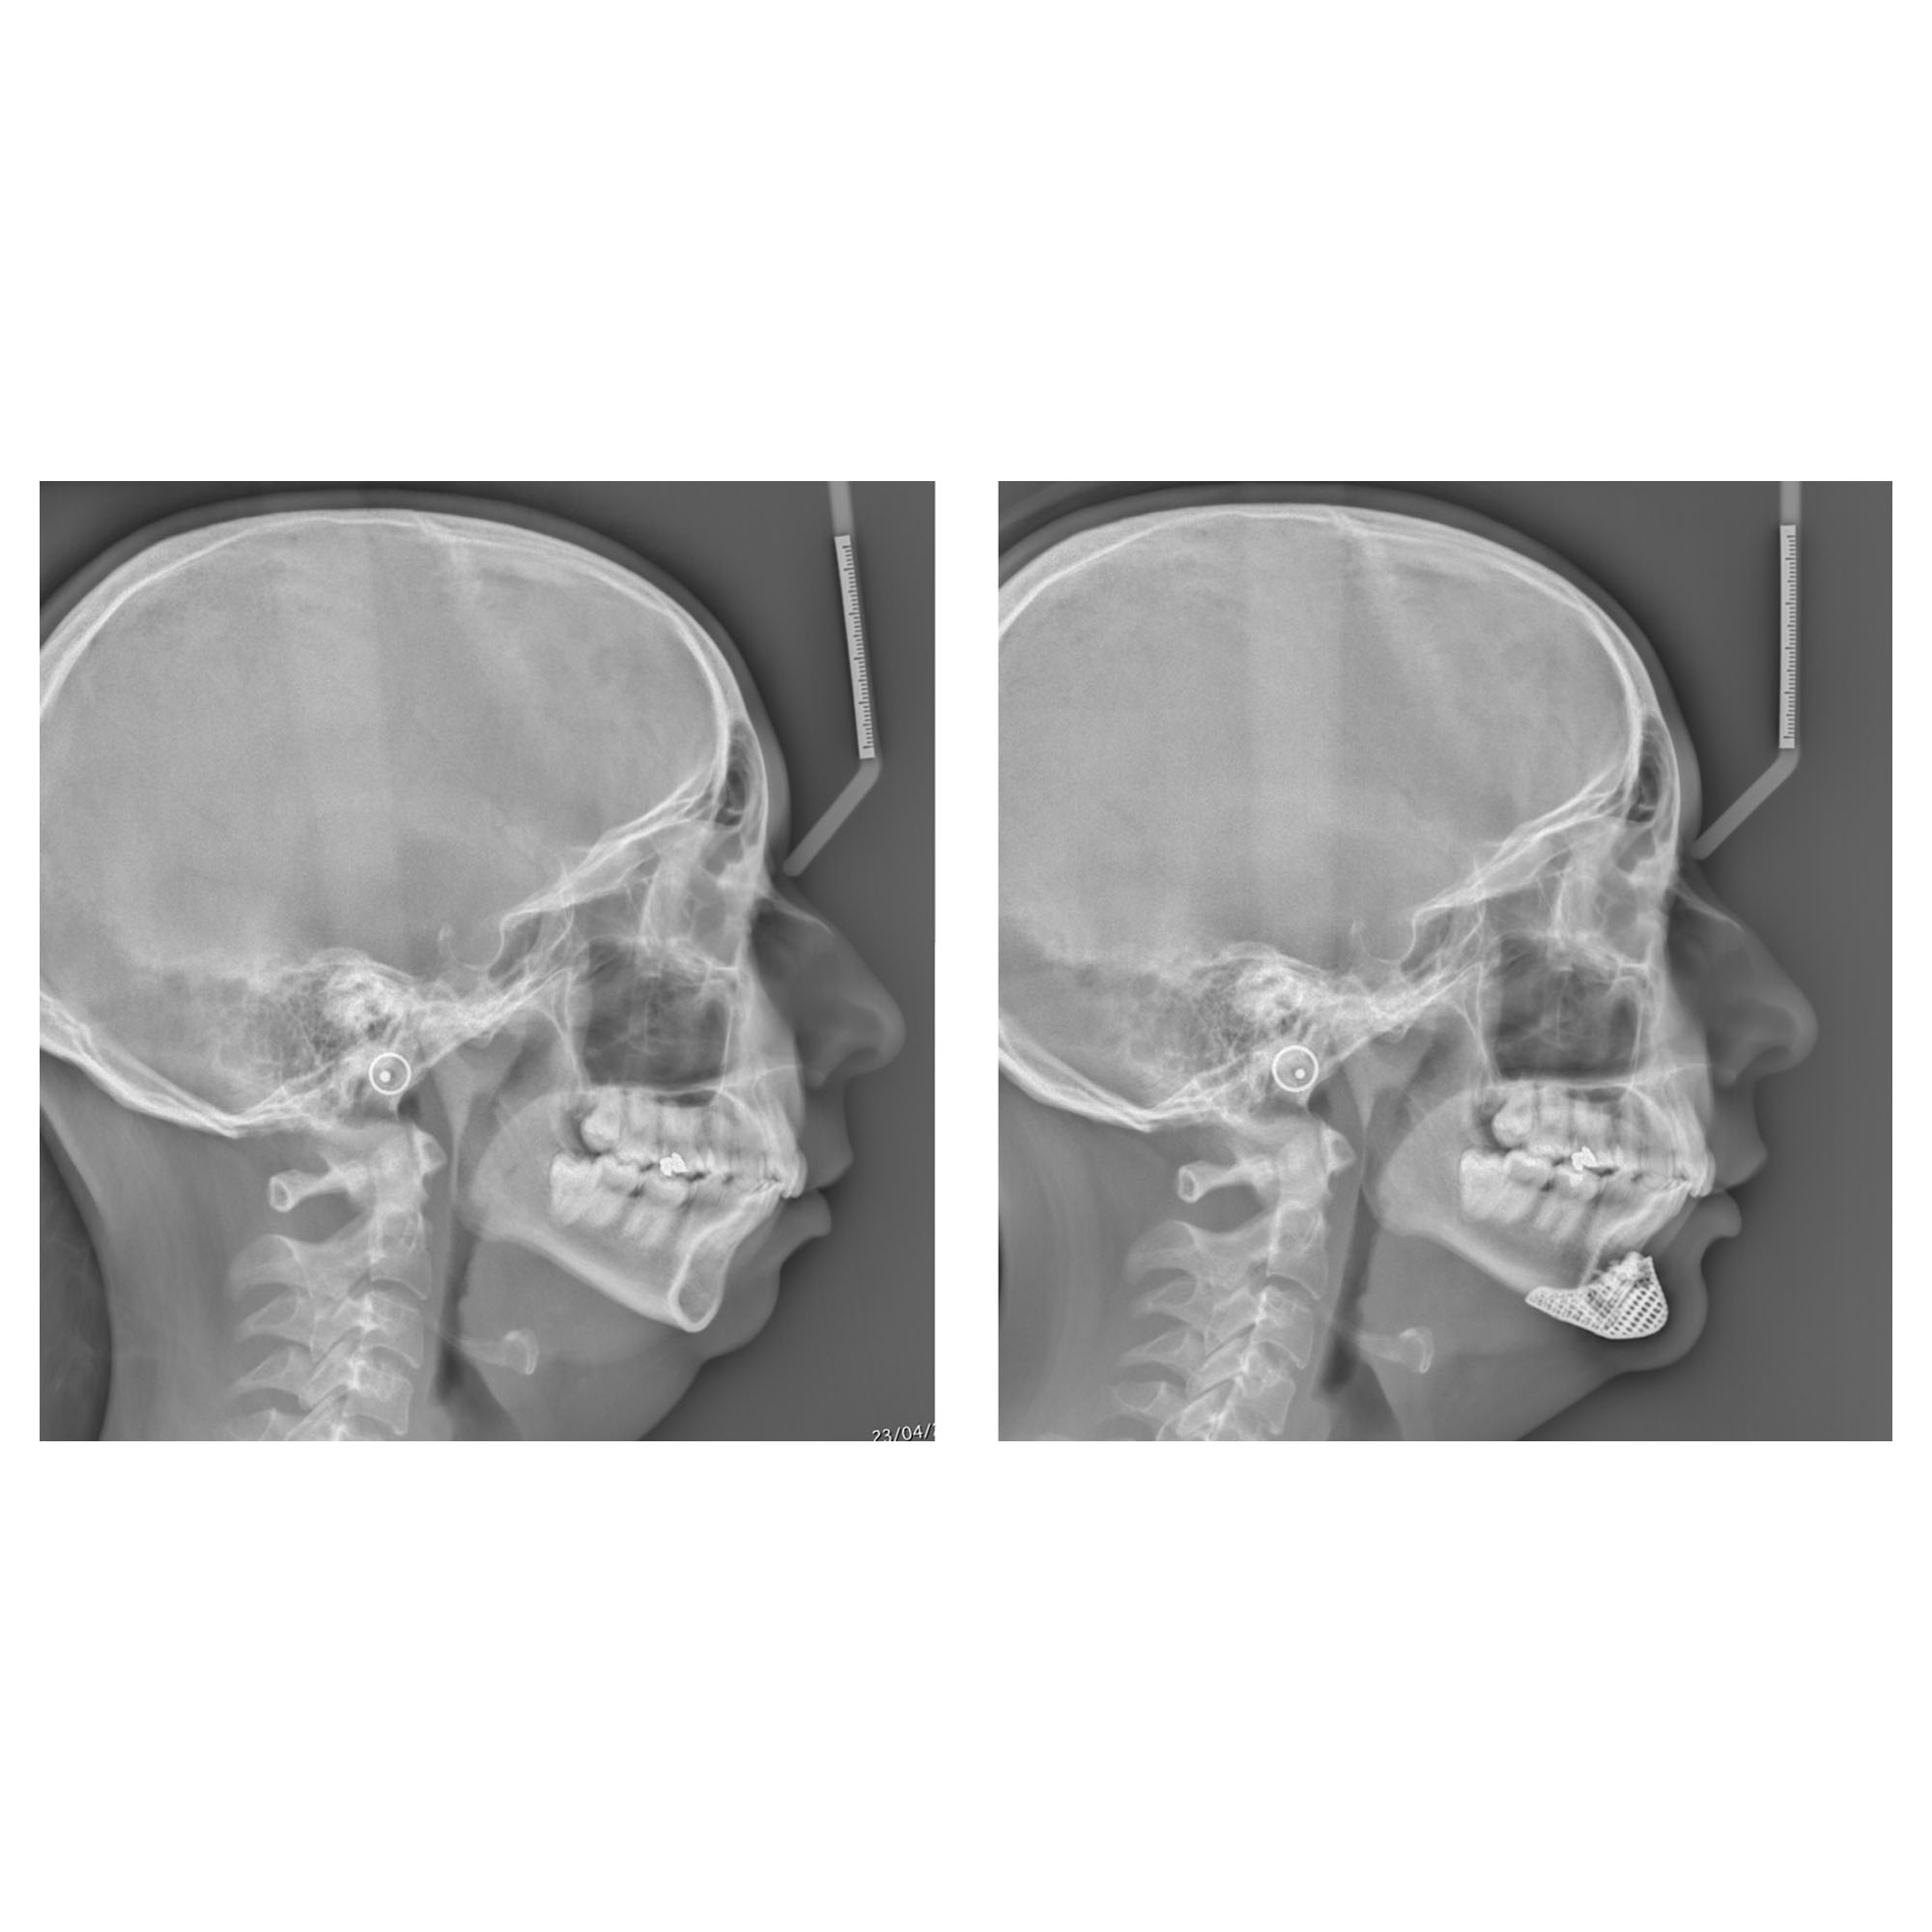

chirurgie du menton radiographies profil avant apres chirurgie du menton abaissement recul

Ci-dessus, on observe les télé-radiographies de profil avant/après d’un patient avec un menton en galoche opéré par le Docteur Thierry Loncle. Après la génioplastie, le recul et l’abaissement du menton a permis d’obtenir un visage plus harmonieux.